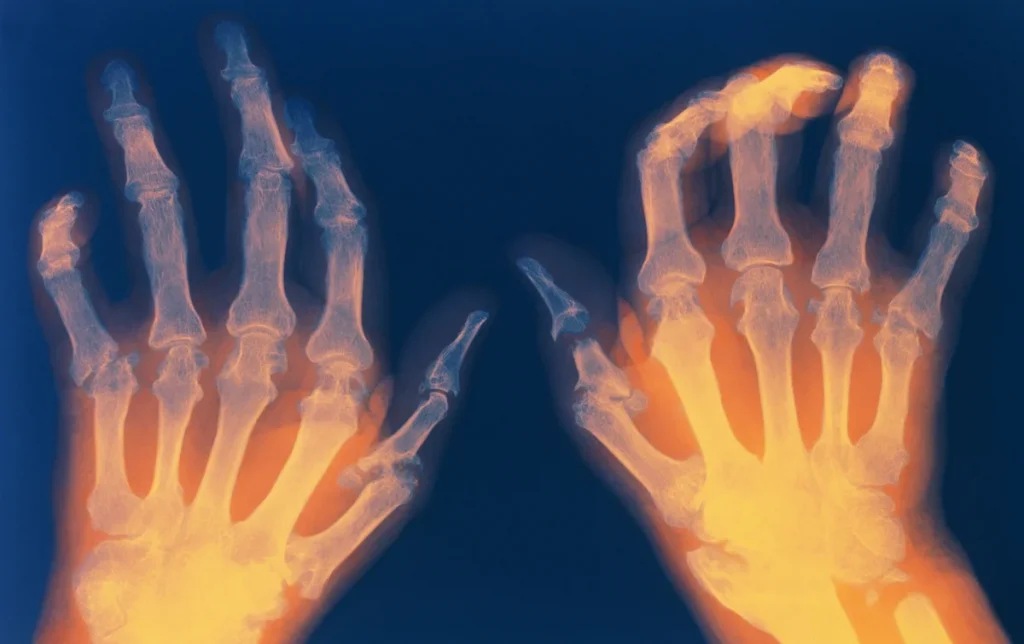

Se revelan crecientes tasas de Artritis Reumatoide (AR) en el mundo y su impacto en adultos jóvenes. Estudio recopila datos entre 1980 y 2021 y deja ver la necesidad de ajustes dietéticos, políticas médicas accesibles y tratamientos innovadores como la terapia celular. Qué dice la investigación.

La investigación asegura que la Artritis Reumatoide se presenta en 17,9 millones de personas en 2021, un aumento del 13% desde 1990.

El análisis sustenta que la carga global de Artritis Reumatoide (AR) en el periodo analizado siguió aumentando y mostró una tendencia a ser más joven y amplia.

Confirma que la Artritis Reumatoide (AR) es un problema creciente de salud pública y que las tasas de prevalencia más altas en Europa Occidental y Norteamérica podrían deberse a mejores capacidades de diagnóstico y acceso a la atención médica.

Por otro lado, revela que el incremento global de casos entre personas mayores de 55 años se alinea con la asociación de la AR con el envejecimiento del sistema inmunitario y la acumulación de inflamación crónica.